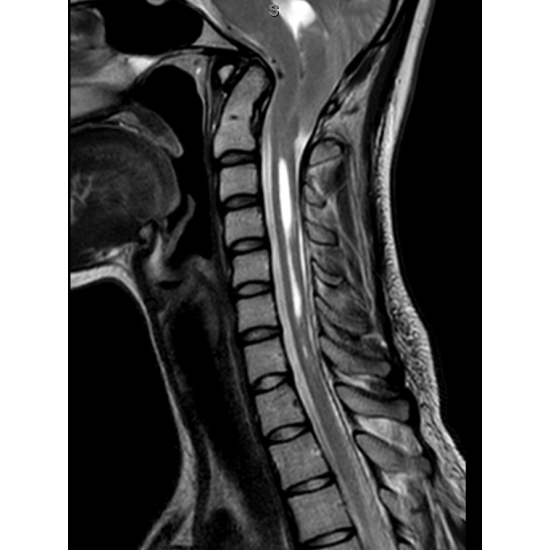

MRI cervical spine without contrast: Chiari 1.5 malformation with extensive syringomyelia of the cervical cord and partially imaged hydrocephalus of the fourth ventricle. Disc preserved in height and signal with no herniation or osteophyte complex C2-T1. Case Photo #5